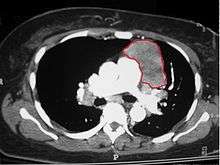

When a thymoma is suspected, a CT/CAT scan is generally performed to estimate the size and extent of the tumor, and the lesion is sampled with a CT-guided needle biopsy. Increased vascular enhancement on CT scans can be indicative of malignancy, as can be pleural deposits.[1] Limited biopsies are associated with a very small risk of pneumomediastinum or mediastinitis and an even-lower risk of damaging the heart or large blood vessels. Sometimes thymoma metastasize for instance to the abdomen.[3]